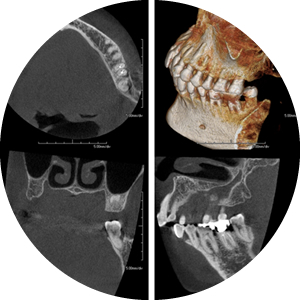

診察・検査

検査には、レントゲン撮影、お口の写真撮影、歯周ポケット、歯の動揺度、プラークのつき方、口臭測定、位相差顕微鏡検査などを行います。

- 14枚法

- 全ての歯の骨吸収状態をくわしく確認できるように、14枚のレントゲンに分けて細かく撮影し、精密な診断を行なっていきます。